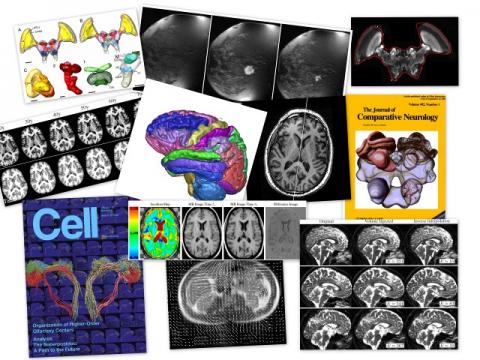

A software toolkit for computational morphometry of biomedical images, CMTK comprises a set of command line tools and a back-end general-purpose library for processing and I/O.

The command line tools primarily provide the following functionality: registration (affine and nonrigid; single and multi-channel; pairwise and groupwise), image correction (MR bias field estimation; interleaved image artifact correction; EPI unwarping), processing (filters; combination of segmentations via voting and STAPLE; shape-based averaging), statistics (t-tests; general linear model).